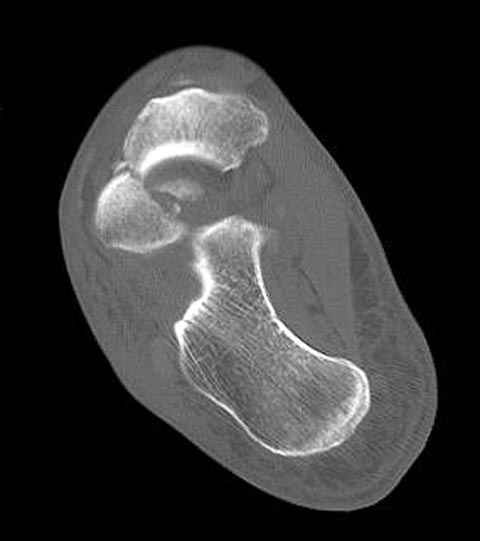

Уважаемые участники русского Ортофорума, поздравляю всех со всеми прошедшими праздниками: Новым годом, Рождеством, Hanukkah, Kwanzaa, желаю участникам всего наилучшего и здоровья.Повреждение таранной кости.Больной 81г автоавария, повреждение таранной кости, здесь снимки. Какие рекомендации?Djoldas Kuldjanov, MDDepartment of Orthopedic SurgerySt. Louis University Medical Center

Вдогонку по поводу перелома таранной кости, больная 81, не страдает диабетом, перелом закрытый, в первый же день поступления ограничились временным наружным фиксатором (как на снимке).

За пару недель насчитал 5 больных с переломом таранной кости, из них двое с двусторонним повреждением.

Из-за отека на стопе тактика лечения у всех была

одинаковая: временная наружная фиксация до спадения отека, при изолированных переломах они выписывались домой и через дней 7 госпитализировались на оперативное лечение.